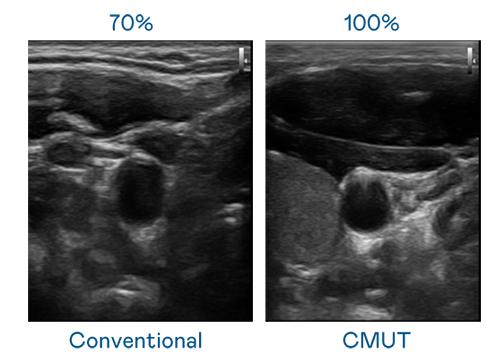

CMUT 技术是一种用电容式微机电元件来产生超音波讯号的技术。与传统 PZT 压电式技术相比,CMUT 频宽增加 30%,更宽频的超音波讯号让影像解析度大幅提升,是实现高影像品质医疗超音波扫描、促进精准医疗发展的关键技术。

大频宽带来超清晰影像

超音波影像的解析度高低,首先取决于探头能发出的讯号频宽。果冻天美乌鸦星空 CMUT 可提供高清晰的超音波讯号,提供高频宽、高灵敏度、影像纹理细节更高的超音波影像,协助医护人员缩短影像判读时间及利用精准的医疗影像进行诊断。